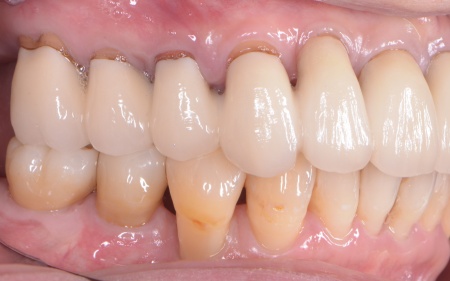

患者様は「できるだけ治療期間を短くしたい」と希望されていることから、右下の第1大臼歯は抜歯即時埋入インプラントを提案しました。 抜歯即時埋入インプラントとは、抜歯と同日に人工歯根「インプラント体」を埋め込む方法です。 これにより、通常のインプラントと比べて治療期間を短縮することができます。 なおこの方法は、骨の量・質・感染の有無・歯ぐきの状態などの条件があり、すべての症例で行えるわけではありません。 また、大臼歯周囲は、歯の周りを保護する硬い歯ぐき「角化歯肉」が不足していました。 手前の小臼歯については「同じ歯の治療を繰り返したくない」とのご希望から、精密補綴治療を提案しました。 それぞれの治療内容を丁寧に説明したところ、すべての治療に同意いただきました。 まず、大臼歯の抜歯から行います。 次に、小臼歯に関しては古い詰め物を取り外し、マイクロスコープを用いて拡大視野のもとで歯の形を整えて型を採り、精度の高いセラミックの被せ物を作製・装着しました。 |

| 治療期間 | 約5ヶ月 |

| 費用 | 約765,000円 (抜歯即時インプラント・角化歯肉移植・セラミッククラウン) |